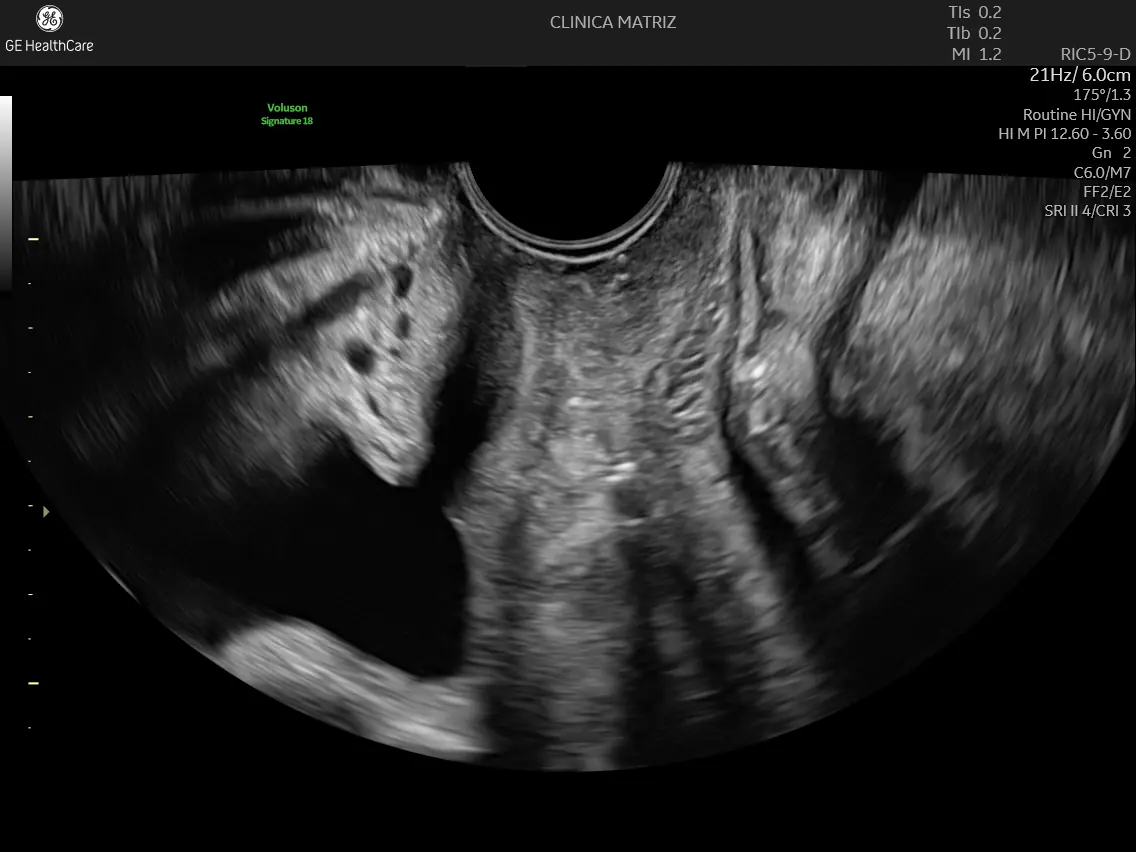

A histerossonossalpingografia é um exame de ecografia ginecológica que permite avaliar a cavidade uterina e a permeabilidade das trompas de Falópio sem recorrer a radiação. Ao contrário de outros métodos, este não exige anestesia e é realizado em ambiente de consulta por um médico ginecologista especializado.

Este é um exame realizado através de ecografia transvaginal. Introduzimos um cateter muito fino e flexível pelo colo do útero para instilar uma solução de contraste específica (espuma). É o movimento deste líquido que nos permite desenhar a anatomia interna e detetar qualquer obstrução.